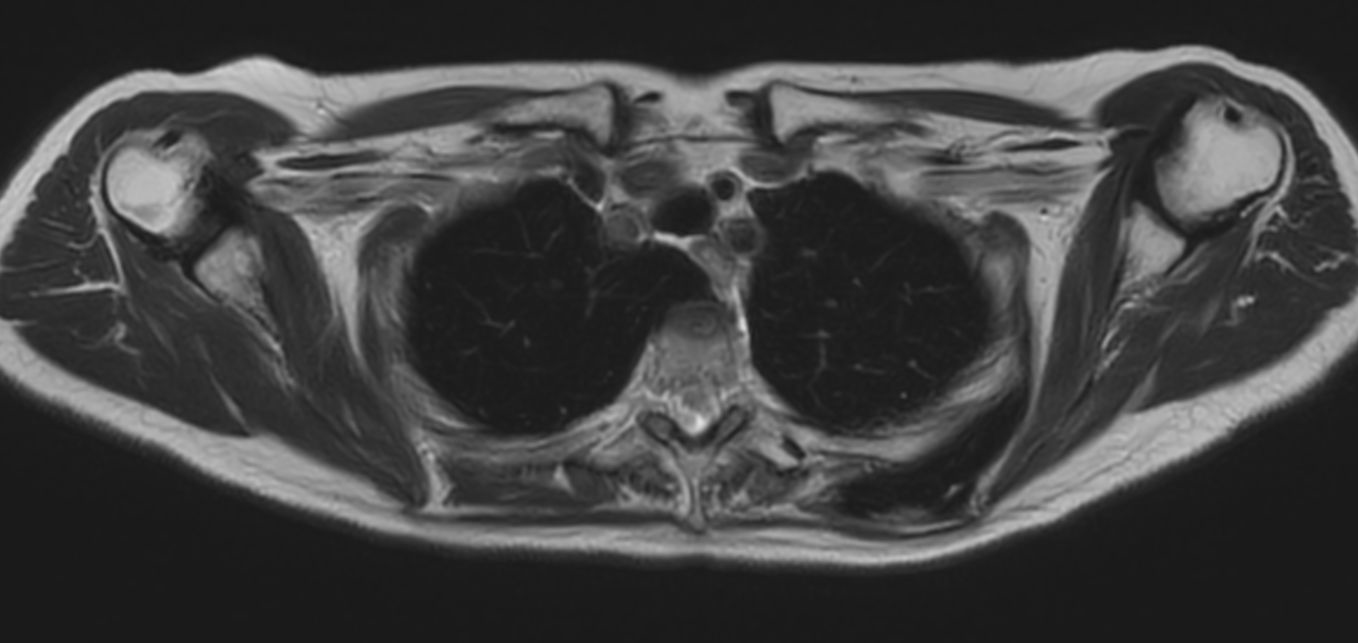

Patient with a thorax soft tissue lesion. ExamCard includes Compressed SENSE to shorten the scan time, MultiVane XD to acquire motion-free diagnostic images, 3D VANE XD helping to reduce motion artifacts during free breathing and 4D FreeBreathing to perform multi-phase contrast-enhanced MRI studies.

T1w FFE 3D VANE XD (In Phase) - Free Breathing